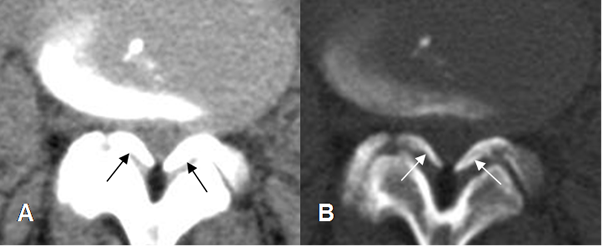

Fig 69. Calcificación de los ligamentos amarillos.

A: TAC axial en ventana de tejido y B: TAC axial en ventana osea. Canal estrecho mixto, con hipertrofia de articulaciones intervertebrales y prominencia de los ligamentos amarillos, los cuales están calcificados.